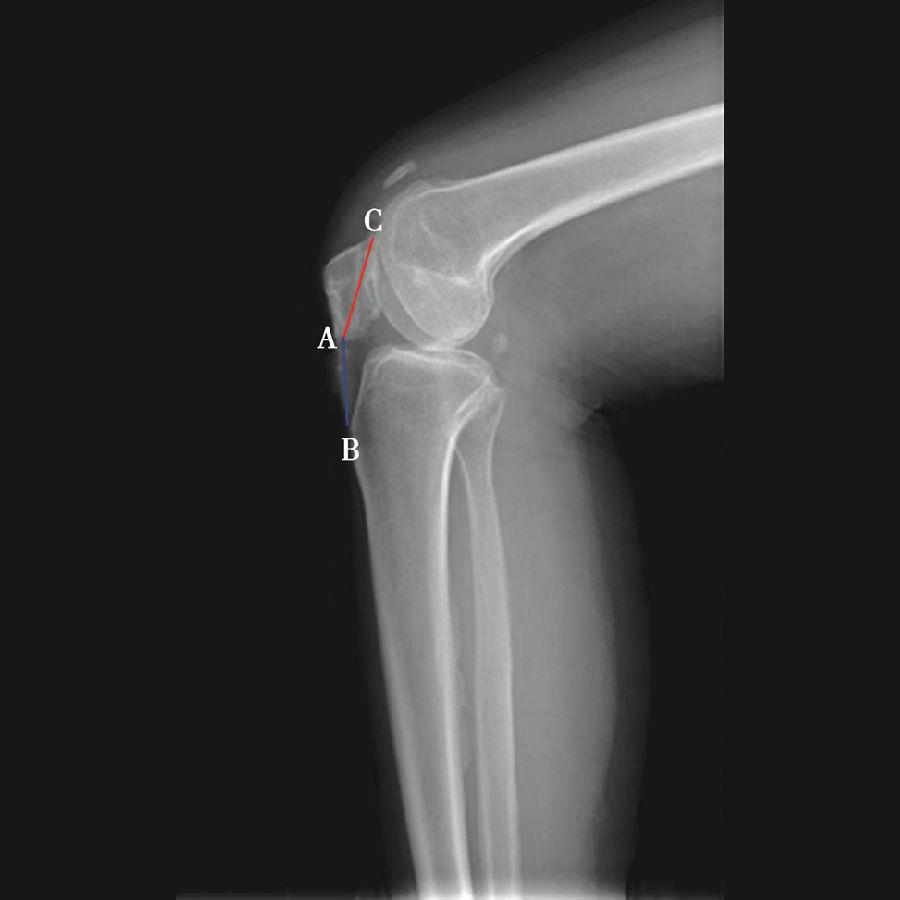

如图示:AB是髌韧带长度,AC髌骨纵轴长度。Insall-Salvati指数=AB/AC(图4)。

图4 Insall-Salvati指数=AB/AC=1.10,为正常髌骨高度

图5 Insall-Salvati指数=AB/AC=1.40,为高位髌骨

但是此法测量髌骨韧带时往往依赖准确的估计胫骨结节与髌骨下极的位置。因此,髌骨下极和胫骨结节的病变都会影响测量的结果,尤其是发生胫骨结节骨软骨炎的患者确定这一位置便更加的困难。此外,该指数不能用于评估胫骨结节向近端或远端移位的效果。因为该指数测量所使用的标记在胫骨结节术后均未发生改变,Insall指数也就不会变化。